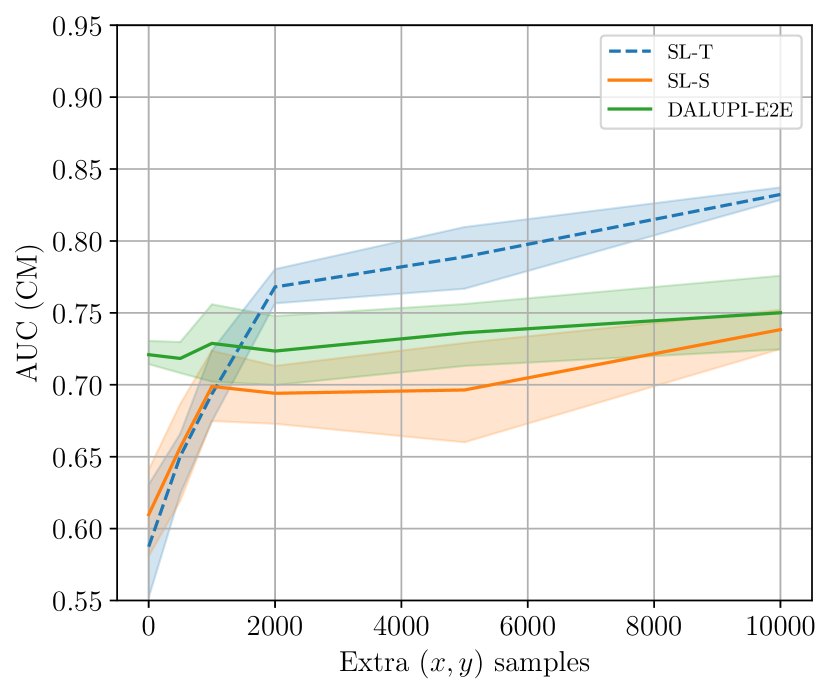

In Table 2 we present the per-class AUCs in the target domain. DALUPI-E2E outperforms all baseline models, including the target oracle, in detecting CM. For ATL and PE, it performs similarly to the other feasible models. That SL-T is better at predicting PE is not surprising given that this pathology is most prevalent in the target domain. In Figure 5(a), we show a single-finding image from the target test set with ground-truth label CM. The predicted bounding box of DALUPI-E2E with the highest probability is added to the image. DALUPI-E2E identifies the region of interest and makes a correct classification. The bottom panel shows the saliency map for the ground truth class for SL-S. We see that the gradients are mostly constant, indicating that the model is uncertain. In Figure 5(b), we show AUC for CM for DALUPI-E2E, SL-S, and SL-T trained with additional examples without bounding box annotations. We see that SL-S catches up to the performance of DALUPI-E2E when a large amount of labeled examples are provided. These results indicate that identifiability is not the primary obstacle for adaptation, and that PI improves sample efficiency.

In Figure 5(b) in Section 5.3, we present AUC for the pathology CM when additional training data are added. In Figure 6, we show the average AUC when additional training data of up to amples are added. We see that, once given access to a much larger amount of labeled samples, SL-S and DALUPI-E2E perform comparably in the target domain.